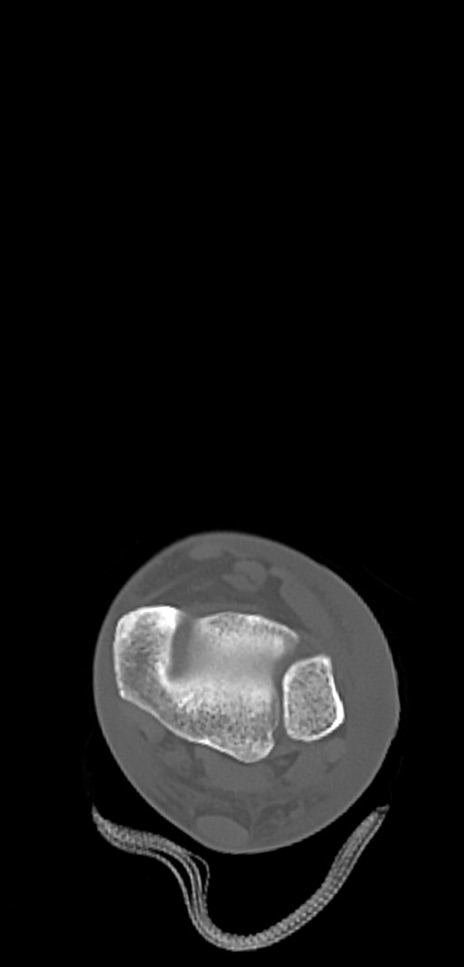

症例37 左足関節CT(横断像)

左足関節CT